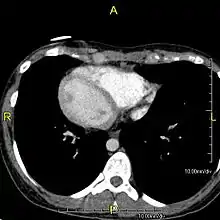

Axial CT image showing dextrocardia and situs inversus in a patient with Kartagener syndrome.

Situs inversus is found in about 0.01% of the population, or about 1 person in 10,000. In the most common situation, situs inversus totalis, it involves complete transposition (right to left reversal) of all of the viscera. The heart is not in its usual position in the left chest, but is on the right, a condition known as dextrocardia (literally, "right-hearted"). Because the relationship between the organs is not changed, most people with situs inversus have no associated medical symptoms or complications.[1]

The condition affects all major structures within the thorax and abdomen. Generally, the organs are simply transposed through the sagittal plane. The heart is located on the right side of the thorax, the stomach and spleen on the right side of the abdomen and the liver and gall bladder on the left side. The heart's normal right atrium occurs on the left, and the left atrium is on the right. The lung anatomy is reversed and the left lung has three lobes while the right lung has two lobes. The intestines and other internal structures are also reversed from the normal, and the blood vessels, nerves, and lymphatics are also transposed.

If the heart is swapped to the right side of the thorax, it is known as "situs inversus with dextrocardia" or "situs inversus totalis". If the heart remains on the normal left side of the thorax, a much rarer condition (1 in 2,000,000 of the general population), it is known as "situs inversus with levocardia" or "situs inversus incompletus".